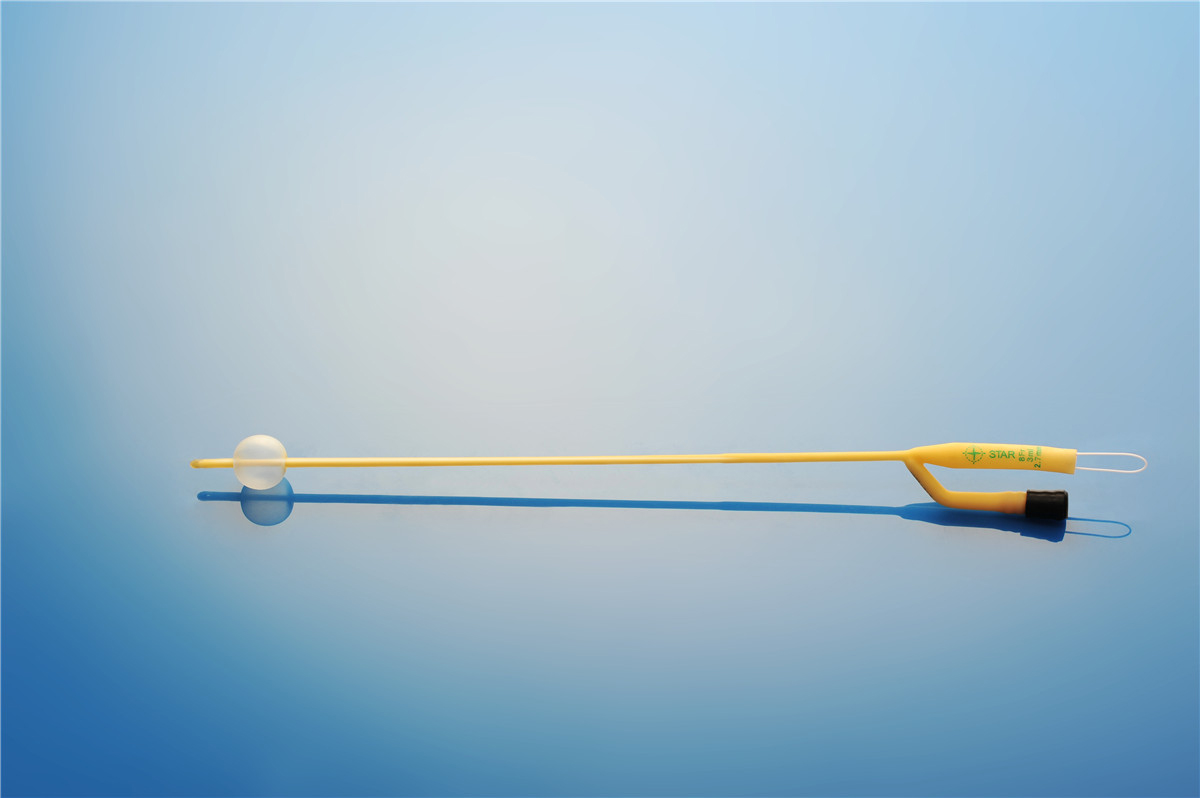

【產品名稱】一次性使用無菌導尿管(取樣型導尿管雙腔兒童型) 【型號】雙腔氣囊取樣型 【規格】:8FR-10FR 【主要結構���、性能】由膠乳為主要原材料制成,可配卡片�。

型號:雙腔氣囊兒童用規格:雙腔氣囊兒童用:8Fr(3mL)���、10Fr(3-5mL)�;結構及組成/主要組成成分:產品由導尿管����、水潤滑包(選配)組成���。雙腔由球囊腔充起錐形接口、排液腔錐形接口����、閥門、管身����、球囊、排液孔組成(尖端有普通尖頭和彎頭區分)����。水潤滑包由無菌水和水刺紗布組成,為輻照滅菌�。導尿管采用天然乳膠和親水潤滑涂...